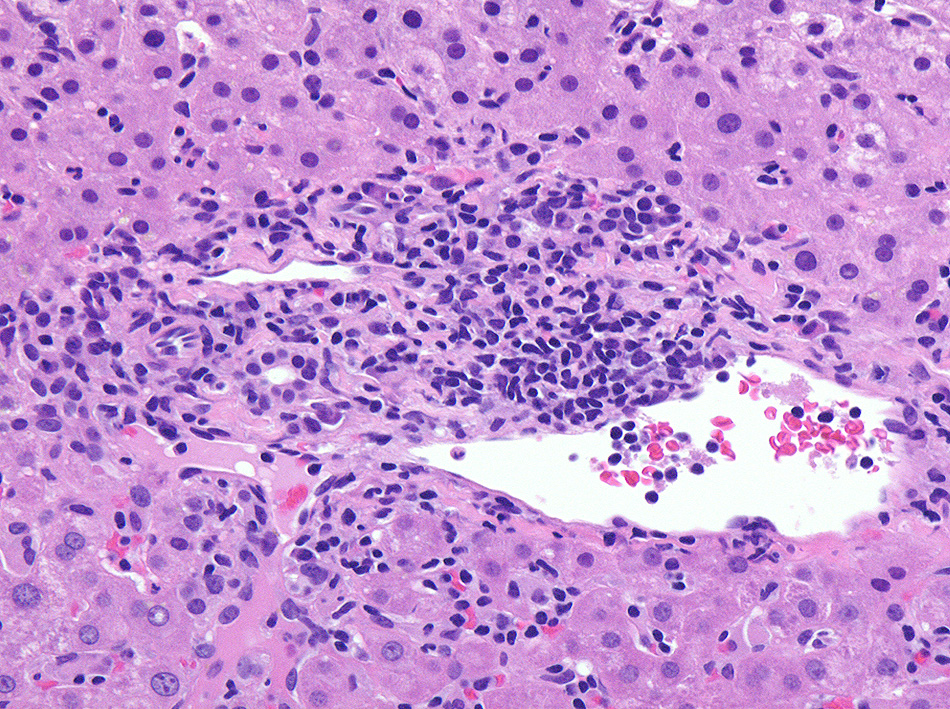

肝臓針生検組織 Virtual Slide--->肝針生検 右クリックで新しいウィンドウ/タブで開くとべんりです。

グリソン鞘, 小葉にリンパ球の浸潤がめだつ。

免疫染色

浸潤リンパ球はCD3+, EBER-ISH+. CD20+細胞はごく少数. CD56, granzymeB陽性リンパ球はほとんど認められない。